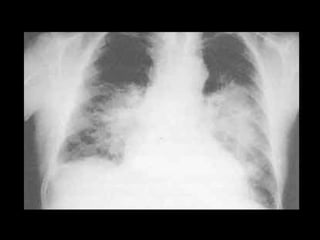

HIPERTENSIÓN VENOCAPILAR PULMONAR La presión de las venas pulmonares es mayor de 8 – 10 mmHg y se transmite en forma retrógada a los capilares pulmonares.  Se produce dilatación de las venas pulmonares.  A mayor presión se produce exceso de líquido en el intersticio pulmonar, en donde se acumula. El acúmulo de líquido en los septa interlobulares se ve como pequeñas y finas líneas horizontales predominantemente en las bases pulmonares  Líneas B de Kerley.

HIPERTENSIÓN VENOCAPILAR PULMONAR El exceso de líquido intersticial interfiere con el drenaje del líquido Se acumula en los septa interlobares (en la radiografía se ven cisuras visibles y derrame pleural), que produce borramiento de los senos costodiafragmáticos. Cuando la HVCP es lenta y crónica, existe vasoconstricción refleja de regiones basales que redistribuye el flujo a las regiones apicales por lo que el ensanchamiento venoso se ve en la mitad superior del tórax   “ Imagen en Asta de Ciervo”

HIPERTENSIÓN VENOCAPILAR PULMONAR Cuando la extravasación de líquido es considerable, el líquido pasa del instersticio a los alveolos (edema alveolar)  “ Edema en Alas de Mariposa ” En HVCP crónica, el ensanchamiento venoso puede ser reversible y el repetido acúmulo de líquido en el intersticio provoca cambios fibróticos que dejan líneas de Kerley o cisuras permanentemente visibles  Da una imagen, que por haberse visto con mayor frecuencia en enfermos con estenosis mitral, se ha llamado ” Pulmón Mitral”.

HIPERTENSIÓN VENOCAPILAR PULMONARLa presión de las venas pulmonares es mayor de 8 – 10 mmHg y se transmite en forma retrógada a los capilares pulmonares. Se produce dilatación de las venas pulmonares. A mayor presión se produce exceso de líquido en el intersticio pulmonar, en donde se acumula. El acúmulo de líquido en los septa interlobulares se ve como pequeñas y finas líneas horizontales predominantemente en las bases pulmonares Líneas B de Kerley.

HIPERTENSIÓN VENOCAPILAR PULMONAREl exceso de líquido intersticial interfiere con el drenaje del líquido Se acumula en los septa interlobares (en la radiografía se ven cisuras visibles y derrame pleural), que produce borramiento de los senos costodiafragmáticos. Cuando la HVCP es lenta y crónica, existe vasoconstricción refleja de regiones basales que redistribuye el flujo a las regiones apicales por lo que el ensanchamiento venoso se ve en la mitad superior del tórax “ Imagen en Asta de Ciervo”

HIPERTENSIÓN VENOCAPILAR PULMONARCuando la extravasación de líquido es considerable, el líquido pasa del instersticio a los alveolos (edema alveolar) “ Edema en Alas de Mariposa ” En HVCP crónica, el ensanchamiento venoso puede ser reversible y el repetido acúmulo de líquido en el intersticio provoca cambios fibróticos que dejan líneas de Kerley o cisuras permanentemente visibles Da una imagen, que por haberse visto con mayor frecuencia en enfermos con estenosis mitral, se ha llamado ” Pulmón Mitral”.